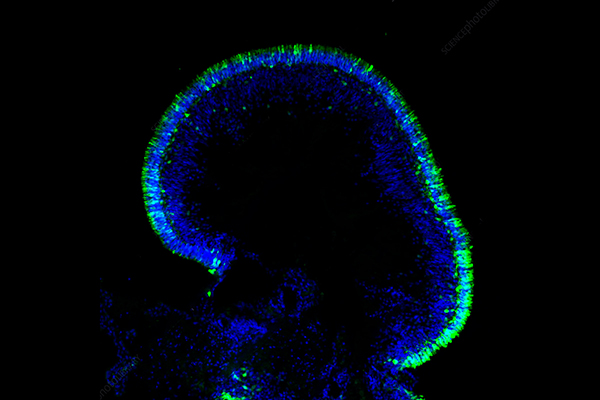

Vasoactive intestinal peptide (VIP) and pituitary adenylate cyclase-activating polypeptide (PACAP) refer to a group of neuropeptides that play crucial roles in maintaining homeostasis in the human body. These neuropeptides are known to be involved in numerous physiological functions, including the regulation of circadian rhythms, neurotransmission, and immune response. In particular, they have been shown to exhibit potent anti-inflammatory and neuroprotective effects.

PACAP binds with high affinity to both PAC1, VPAC1 and VPAC2 receptors and its activity is believed to be predominantly neuroprotective.Fig 1. PACAP, VIP and their downstream effects.1

Despite their potential therapeutic applications, the VIP and PACAP pathways remain poorly understood, and their dysregulation has been implicated in various diseases, including migraine, Alzheimer's disease, and inflammatory bowel disease. While a significant body of research has been conducted on VIP and PACAP, the underlying mechanisms of their effects on human physiology and disease pathogenesis remain largely unknown.